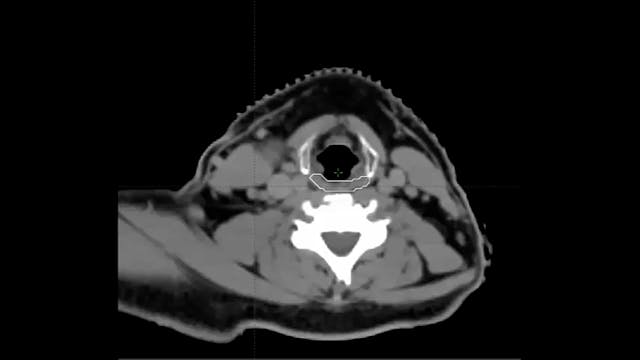

02/28/2022 - Dr. David Sher - Radiation Oncology - Head and Neck

Chartrounds US - Head and Neck Cancer

Osteoradionecrosis